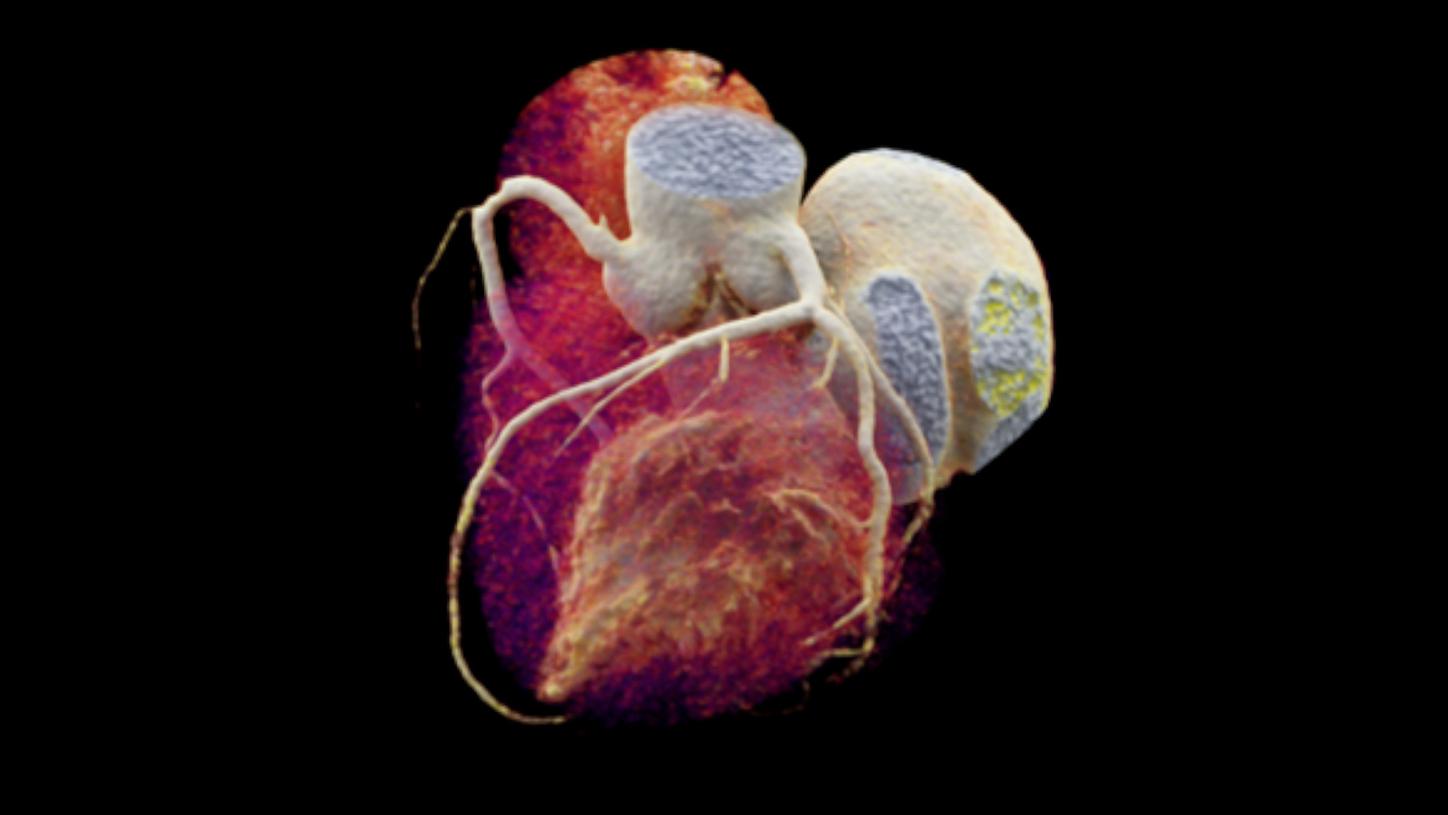

Navin PJ, Venkatesh SK. Hepatocellular Carcinoma: State of the Art Imaging and Recent Advances. J Clin Transl Hepatol. 2019 Mar 28;7(1):72-85. doi: 10.14218/JCTH.2018.00032